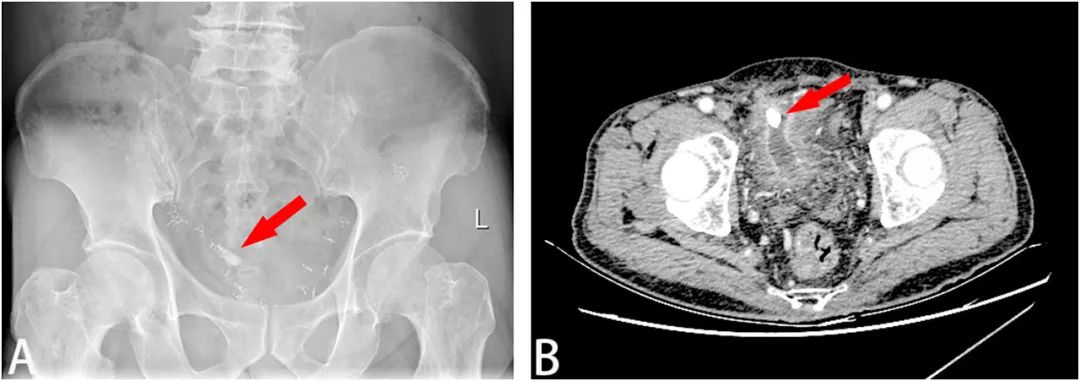

患者男,83岁,因持续性尿路感染入院,自称夜尿7-8次/晚,排尿困难,偶有肉眼血尿。2009年,患者曾接受双侧腹股沟疝修补术;3月前,患者接受了经尿道前列腺电切术。入院后,医生对患者进行了全面的检查。尿常规检查显示血尿和脓尿,但尿培养未发现细菌或真菌。腹部平片和超声检查均显示膀胱结石(图1A)。

图1 (A)腹部平片显示膀胱结石(红色箭头);(B)增强CT显示附着在膀胱前壁的结石(红色箭头)

最初医生认为是膀胱憩室结石。进一步行增强CT检查显示,膀胱前壁上附着一大小约17×14×10mm的结石,骨盆内有多个金属钉,怀疑是用于固定补片的手术钉(图1B)。三维重建CT(3D-CT重建)显示补片侵蚀膀胱,结石与网片粘连紧密(图2)。膀胱镜检查证实膀胱结石的存在,结石周围有红斑性病变,但未发现补片。病变活检显示炎症反应,无恶性肿瘤。结合症状、病史和检查结果,医生最终做出“腹股沟疝修补术后补片移位致膀胱结石形成”的诊断。